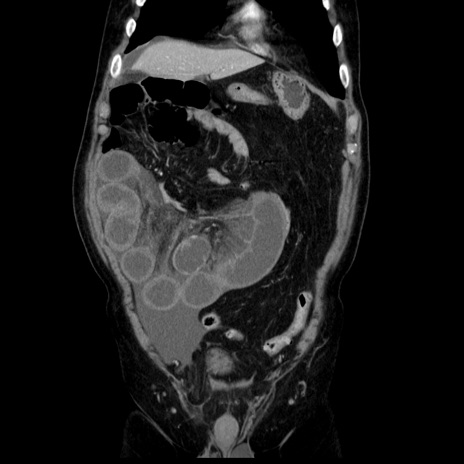

症例30(冠状断像)

【症例】80歳代男性

【主訴】臍周囲痛

【現病歴】約6時間前から臍下部痛が出現。次第に腹部膨隆・背部痛も生じてきたため来院。背部痛の場所は変化しない。

【既往歴】腎盂腎炎

【身体所見】意識清明、BT 36.3℃、BP  131/87mmHg、P 87bpm、SpO2 100%(RA)、臍周囲自発痛・圧痛あり、反跳痛なし、自発痛部位に一致して板状硬あり、腹部膨隆、腸雑音減弱、CVA tenderness両側陰性。

【データ】WBC 19600、CRP 0.33

横断像